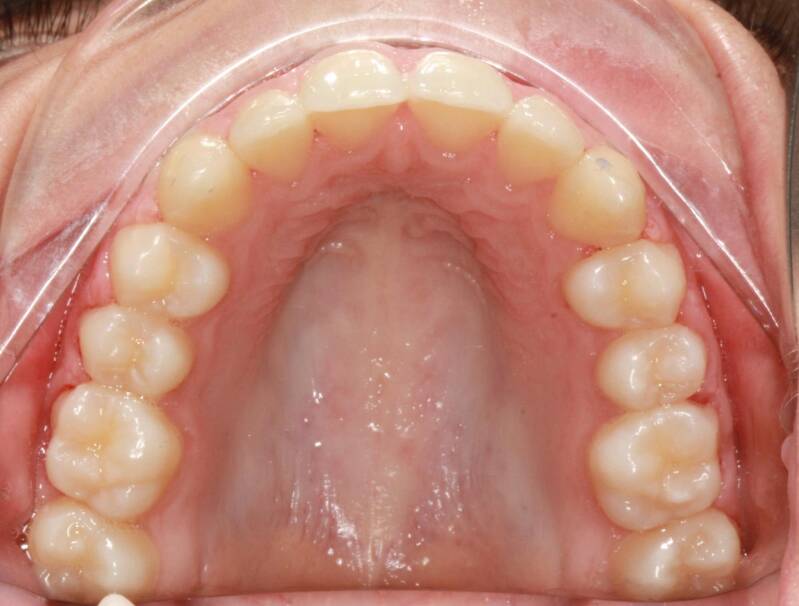

FOTO FINALI DOPO 24 MESI CIRCA DI TERAPA ORTODONTICA FISSA

Abbiamo appena portato a termine questo caso che presentava in arcata superiore il primo premolare di sinistra completamente fuori arcata sovrapposto al secondo premolare ed il canino ruotato.

in arcata inferiore invece abbiamo estratto il secondo molare di sinistra perso per carie deostruente e mesializzato il terzo molare in modo da chiudere lo spazio e non ricorrere all'inserimento di protesi implantare.